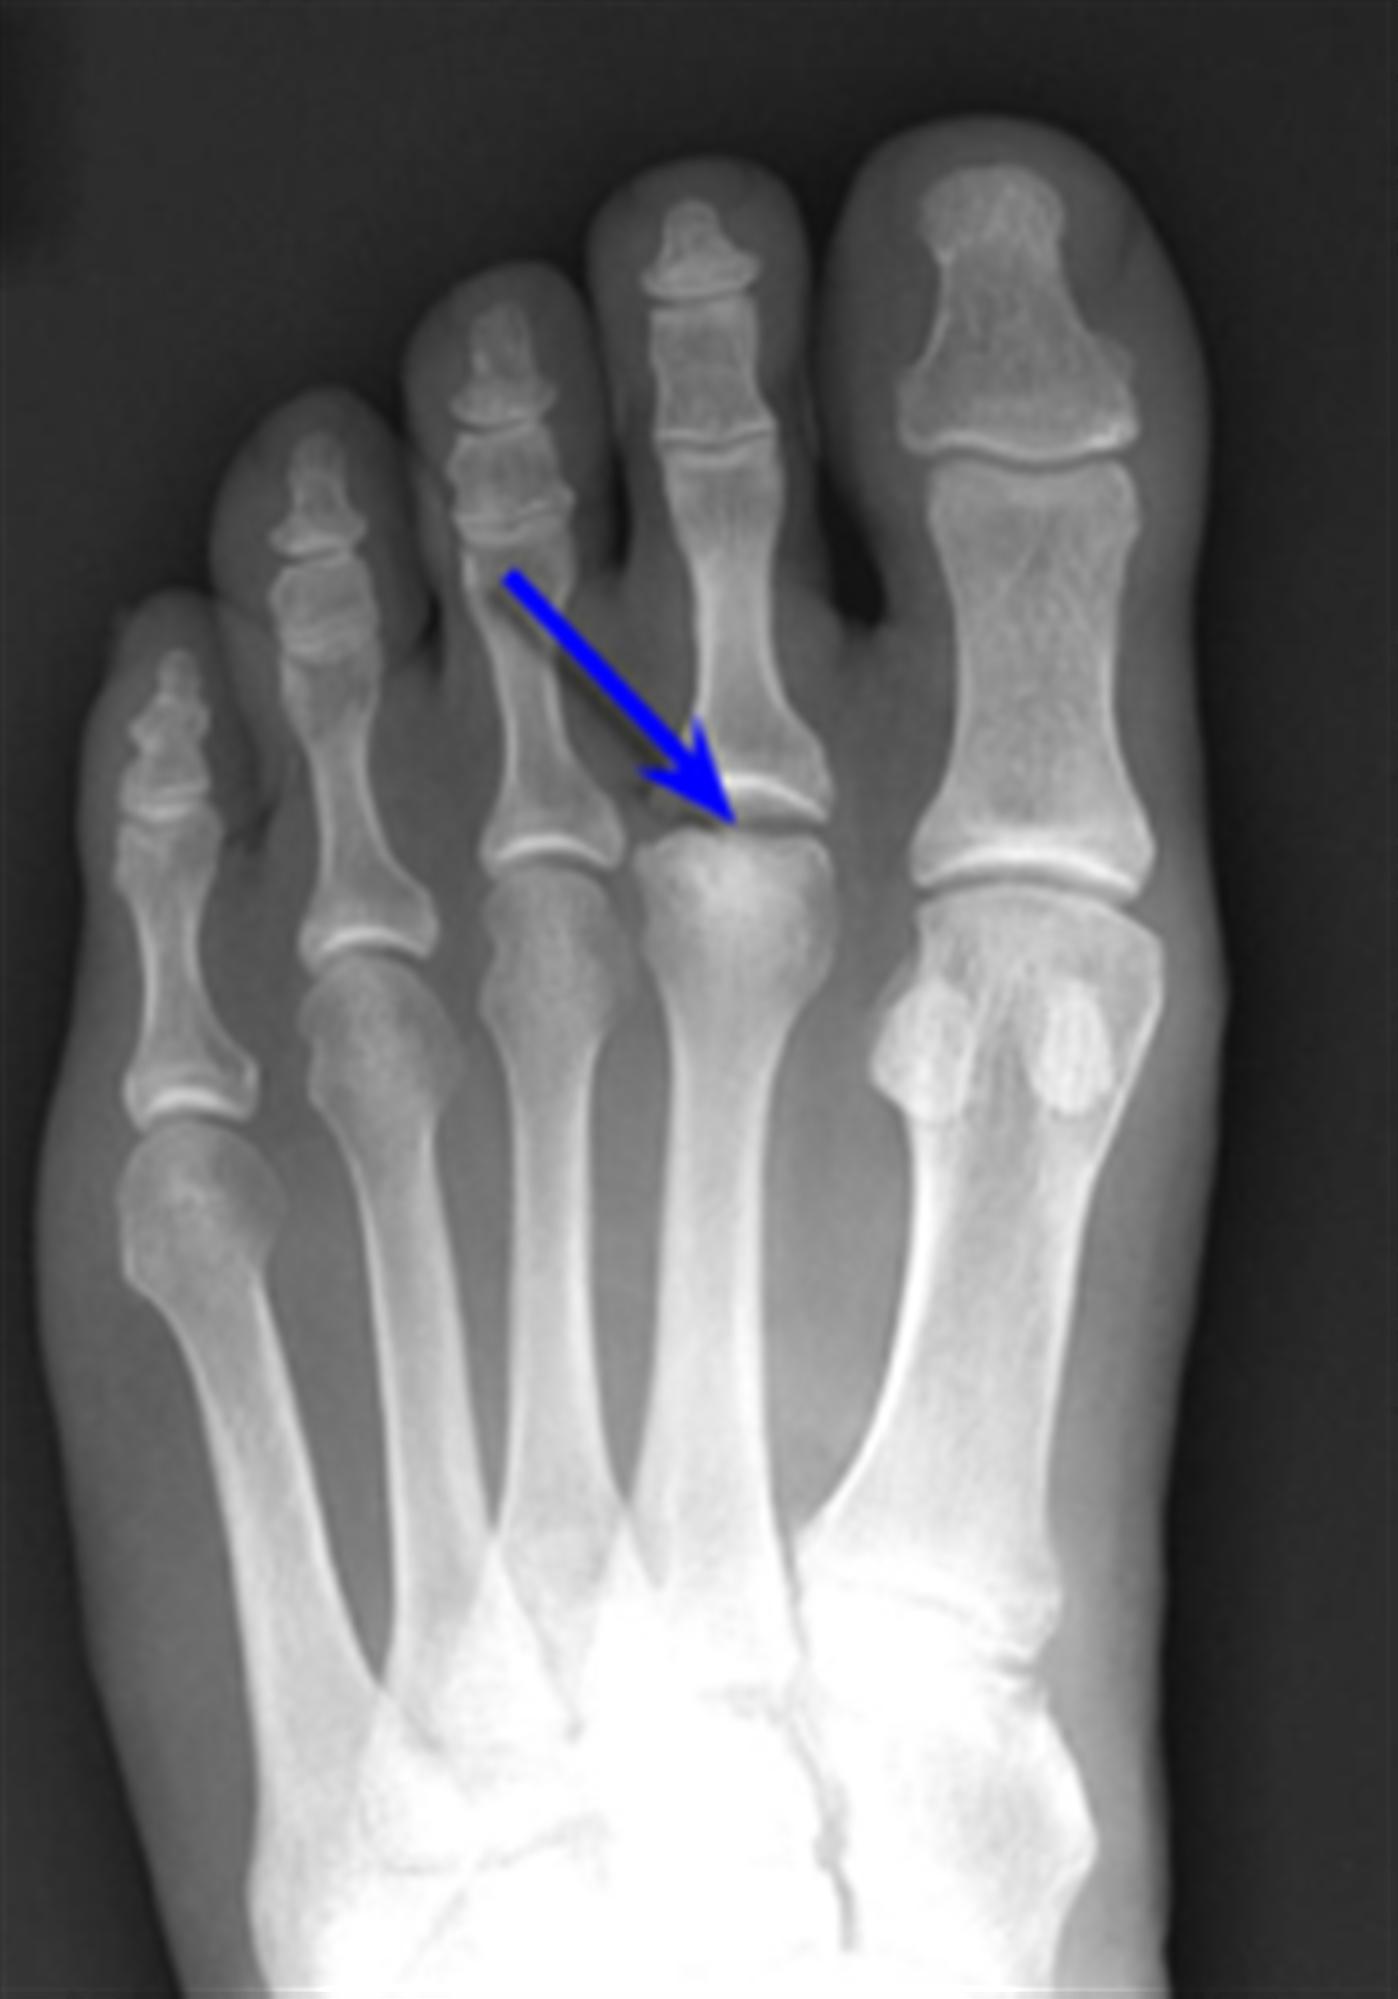

Freiberg's Disease Foot & Ankle Orthobullets Kohlers Disease Kohler disease is a rare, painful bone disorder of a child’s midfoot most commonly seen between two and nine years of age. Learn about its epidemiology, pathology,. Kohler disease is a disease only seen in pediatric patients. Learn how it is diagnosed,. Kohler’s disease is a rare condition that affects the navicular bone in the foot and causes pain, swelling,. Kohlers Disease.